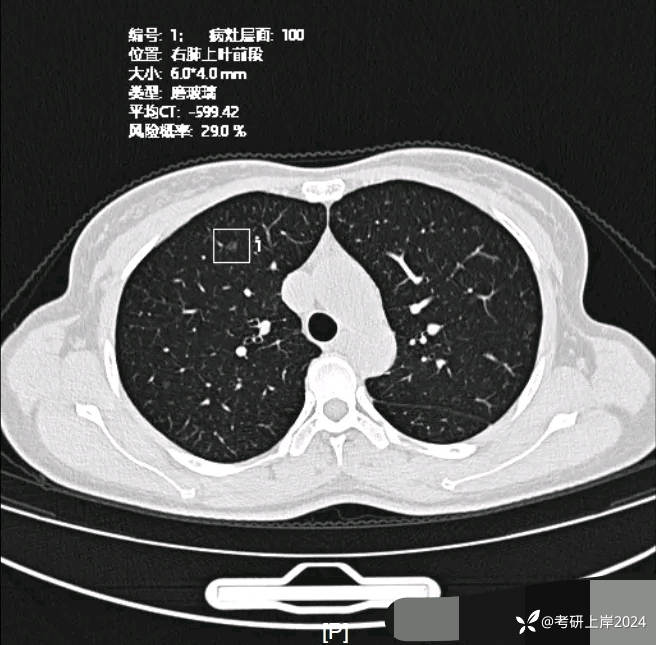

患者最近的检查有AI辅助诊断意见,找出的病灶分别如下:

病灶1:右上叶长径8毫米纯磨玻璃结节,边上有微小血管贴着,整体轮廓较清,怕哪样欠均匀。考虑不典型增生或原位癌可能性大;

病灶5:右上叶微小磨玻璃结节,轮廓较清,考虑肺泡上皮增生可能性较大;

病灶6:左上叶微小磨玻璃结节,轮廓较清,考虑肺泡上皮增生可能性较大;

病灶8:右上叶微小磨玻璃结节,轮廓较清,考虑肺泡上皮增生可能性较大;

病灶14:右上叶很淡密度微小磨玻璃结节,轮廓较清,考虑肺泡上皮增生可能性较大;